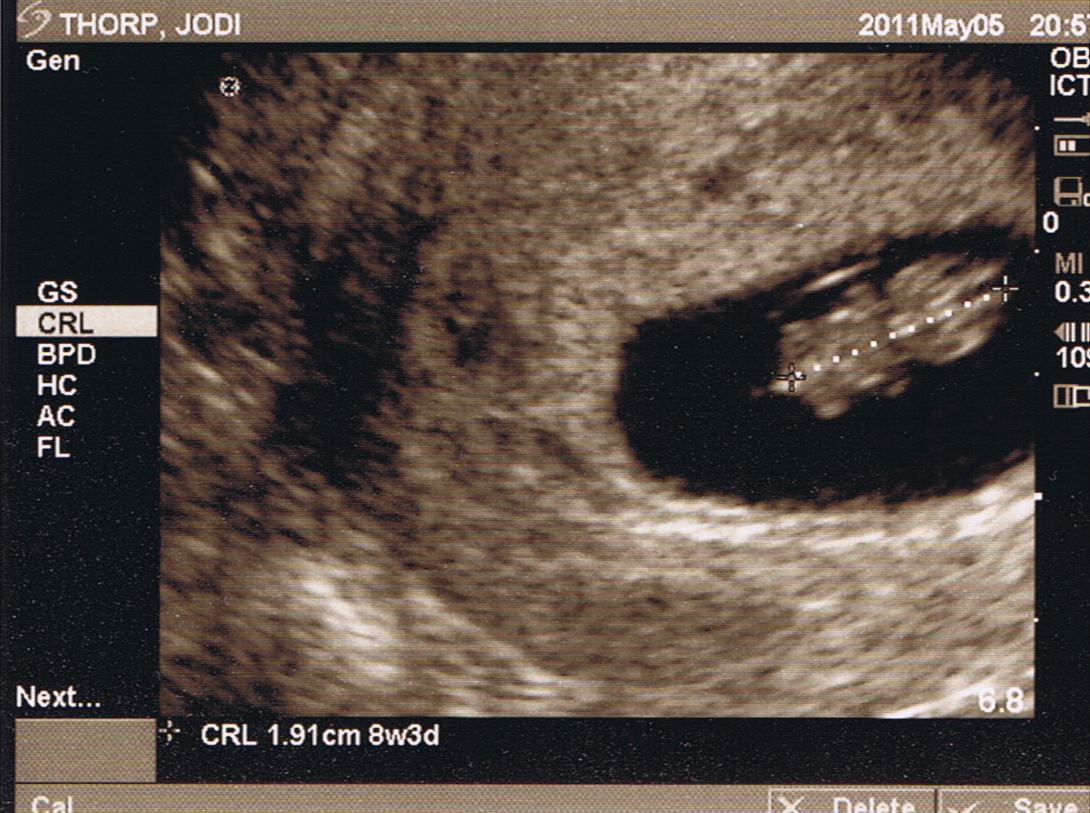

The photo above was the highlight of the hour or more we spent in a dimly lit room with the sonographer. It was worth the wait, but to be honest, I was more excited about these two images:

These show our baby at just eight weeks of development. We’re looking down on him or her from above, with an absolutely Thorpian head to the right, and a torso with four tiny limbs extending to the left and down in the lower image. This was a thrill, not only because we lost a little one last fall and were hoping for an “all systems go!” from our doctor, but because there on the screen was a tiny person, less than two centimeters long, with a beating heart and legs and arms that moved independently of any thought or command from Jodi or me. A child the size of my fingertip who, just before Christmas, we will be blessed to welcome and trusted to raise.

This was made clear again to me when I saw our tiny infant, wriggling in amniotic bliss, at eight weeks of development. Jodi had no say in the flailing of those tiny arms and legs, and that tiny heart beat in part because of, but not for, her. No choice on her part, short of violence, could have stopped it.